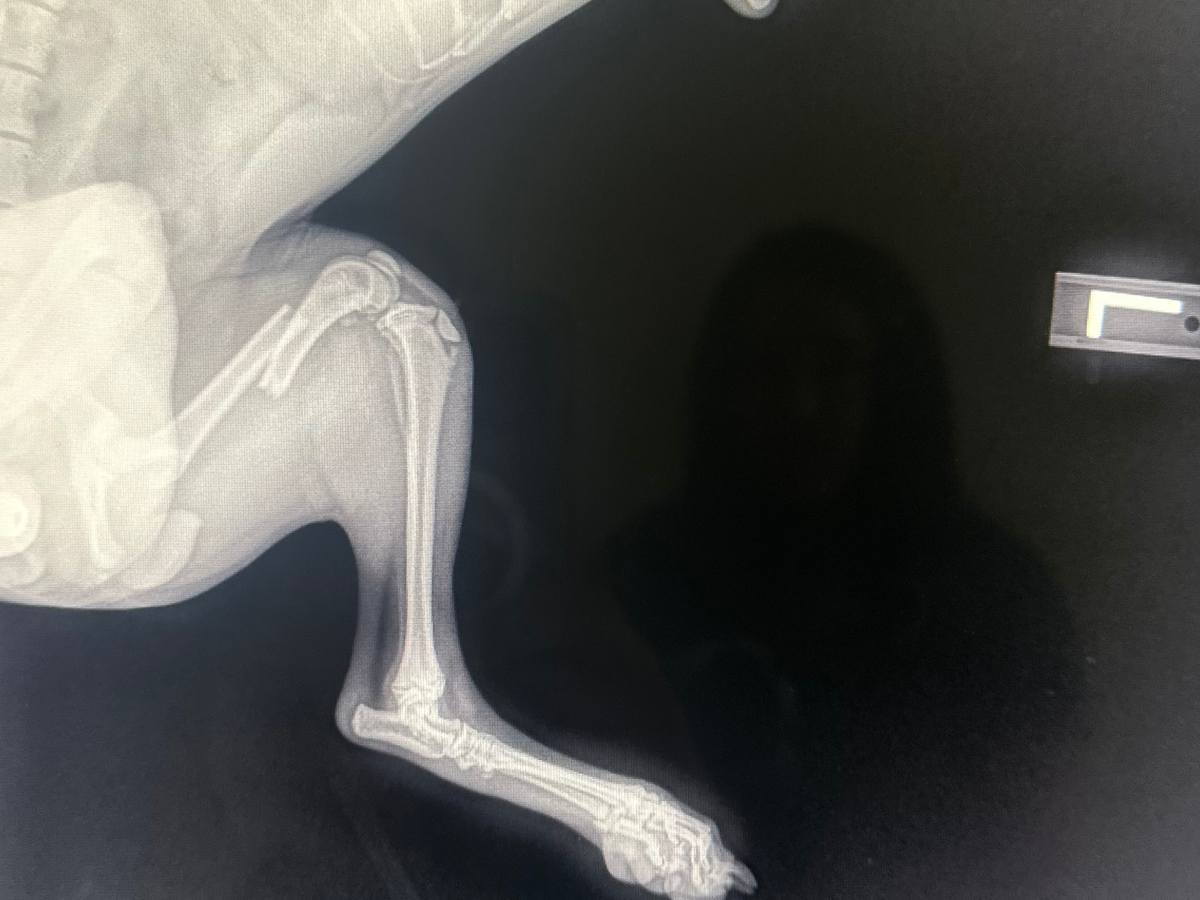

Help Baby Aiko undergo surgery for a Fractured leg.

my little baby Aiko is 6mo. she fell from the couch and fractured her femur bone. it broke my heart when i heard her cries. shes only 8lbs. shes in pain and she got pains meds for the time being. the next step would be surgery to repair the fracture and its really expensive.